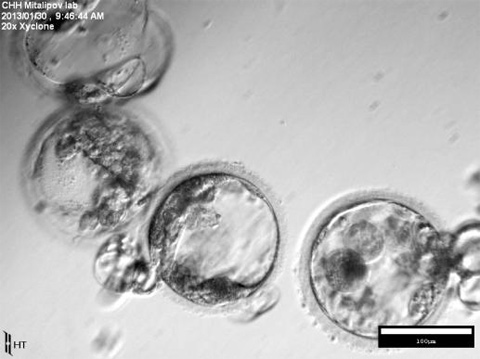

- 韓国で行き詰まった幹細胞研究、日本で開花 2017/07/22 07:03

- 「ES細胞論文不正」の黄禹錫氏、22年を経て「最高科学技術人賞」の受賞取り消し 2026/07/16 11:35